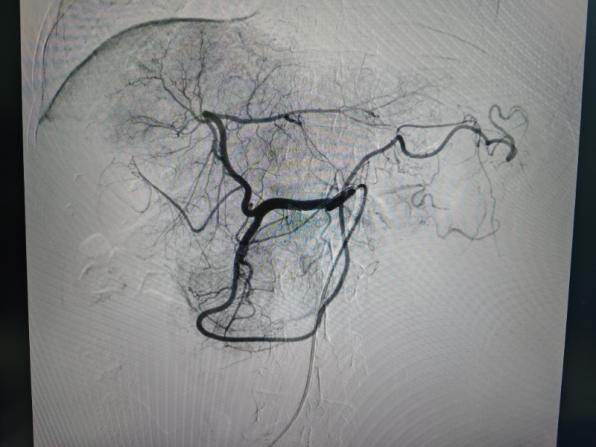

2025年2月20日按照治疗计划,王瑞涛副主任医师行精细化经导管肝动脉化疗药物灌注栓塞术(TACE),术中彻底栓塞肿瘤供血分支动脉,并注入碘化油及化疗药物杀灭肿瘤,术后患者耐受尚可,肝功轻微波动。TACE术后12天(2025年3月5日)经过术前评估,张晓刚主任医师行腹腔镜门静脉右支结扎+放射性粒子植入术,进一步控制肿瘤同时促进肝左叶增大,TACE术后17天(2025年3月10日)开始给予口服靶向药(仑伐替尼)联合免疫治疗(普特利单抗)。

TACE术后28天影像学检查

与2025-02-18日腹部增强片对比示:1.肝右叶多发低密度结节,考虑胆管癌,最大病变内多发颗粒状致密影,考虑介入术后改变,较前病变内坏死增多。肝中静脉局部走行于病灶边缘,管腔未见明显受侵。2.门脉右支起始处少许癌栓,远端未见显影,考虑治疗后改变。3.脾脏缺如;胆囊继发性改变,胆囊窝积液。肠系膜间可见多发稍大淋巴结。